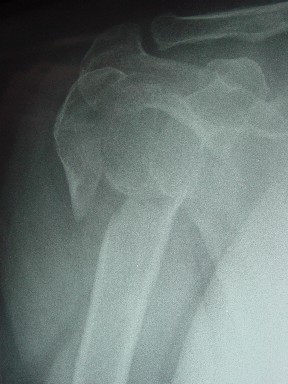

Давайте представим себе состояние манжетки вращателей после вывиха плеча, а еще и с отрывным переломом бугров. Головка может и прирастет, еесли не будет аваскулярного некроза, но хорошего функционального результата не ждите.

Висеть будет красиво. У людей физически активного периода жизни нужно открыть, восстановить костную анатомию и восстановить сухожильный аппарат.

Клинические снимки - 3 недели после операции